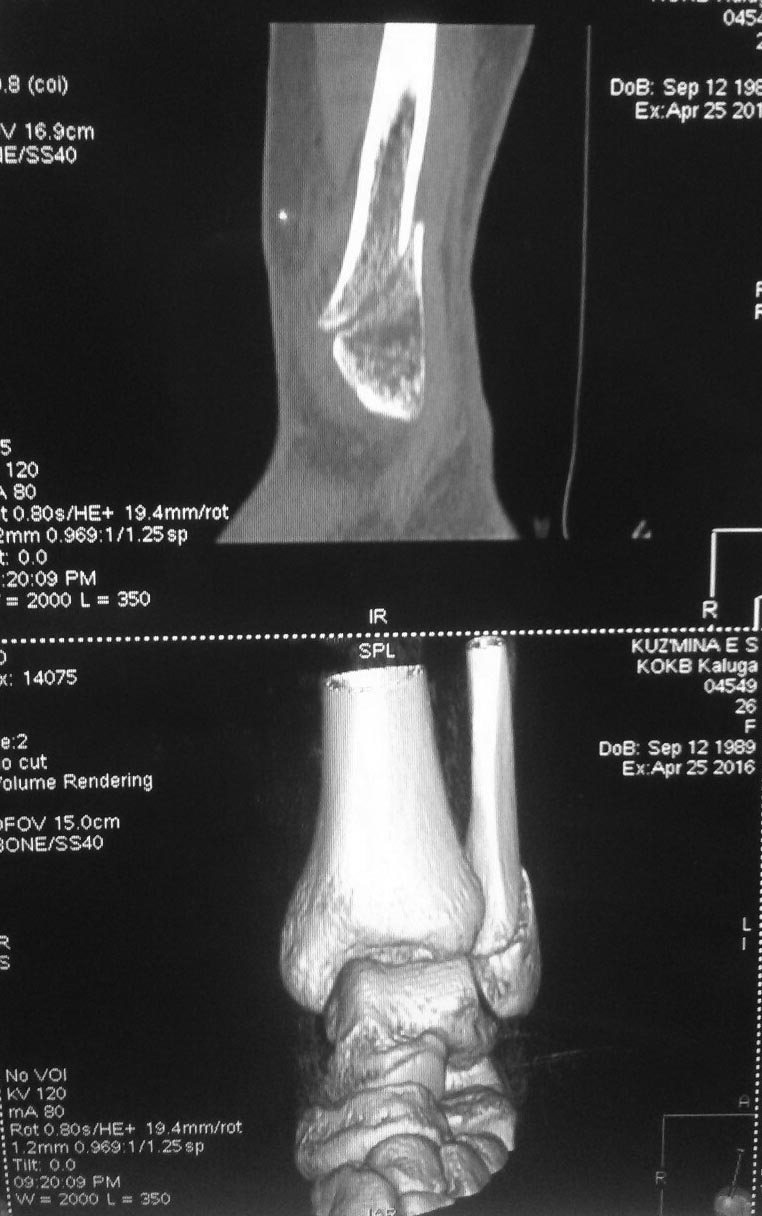

Очень нужен совет,Девушка 27 лет, 19 февраля 2016 года получила перелом н\лодыжки со смещением и надрывом дельтовидной связки.

Сделали репозицию, загипсовали. 30 марта сделали рентген и сняли гипс, не смотря на то что в заключении врача рентгенолога было написано "костной мозоли не выявлено". Врач сказал давать потихоньку нагрузку и назначил физиопроцедуры (лфк и лазер). 20 апреля пришла на прием и попросила проверить ногу еще раз, т.к. поднималась температура и очень болела нога. Отправили на СКТ(снимки прилагаю) Врач посмотрев их сказал что ждем 12 мая еще раз придешь на прием посмотрим, прописал таблетки Осталон и опять физиопроцедуры (грязи и электрофорез с кальце-хлором).Сейчас хожу с палочкой и в фиксирующей повязке (так нога меньше отекает за день).

Подскажите, может, имеет смысл обратиться к другому врачу? Т.к. там где делали СКТ 3 раза спросили ходила ли я вообще в гипсе.